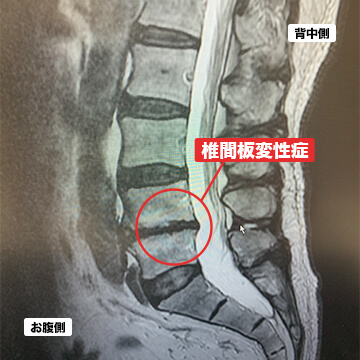

- 椎間板変性症

椎間板変性症とは、椎間板と呼ばれる組織に傷が入り、中の髄核が漏れ出して硬くなることで椎間板が変形してしまう状態を言います。変形が進行すると椎間板ヘルニアになることもあります。主に腰痛の症状が多いとされています。